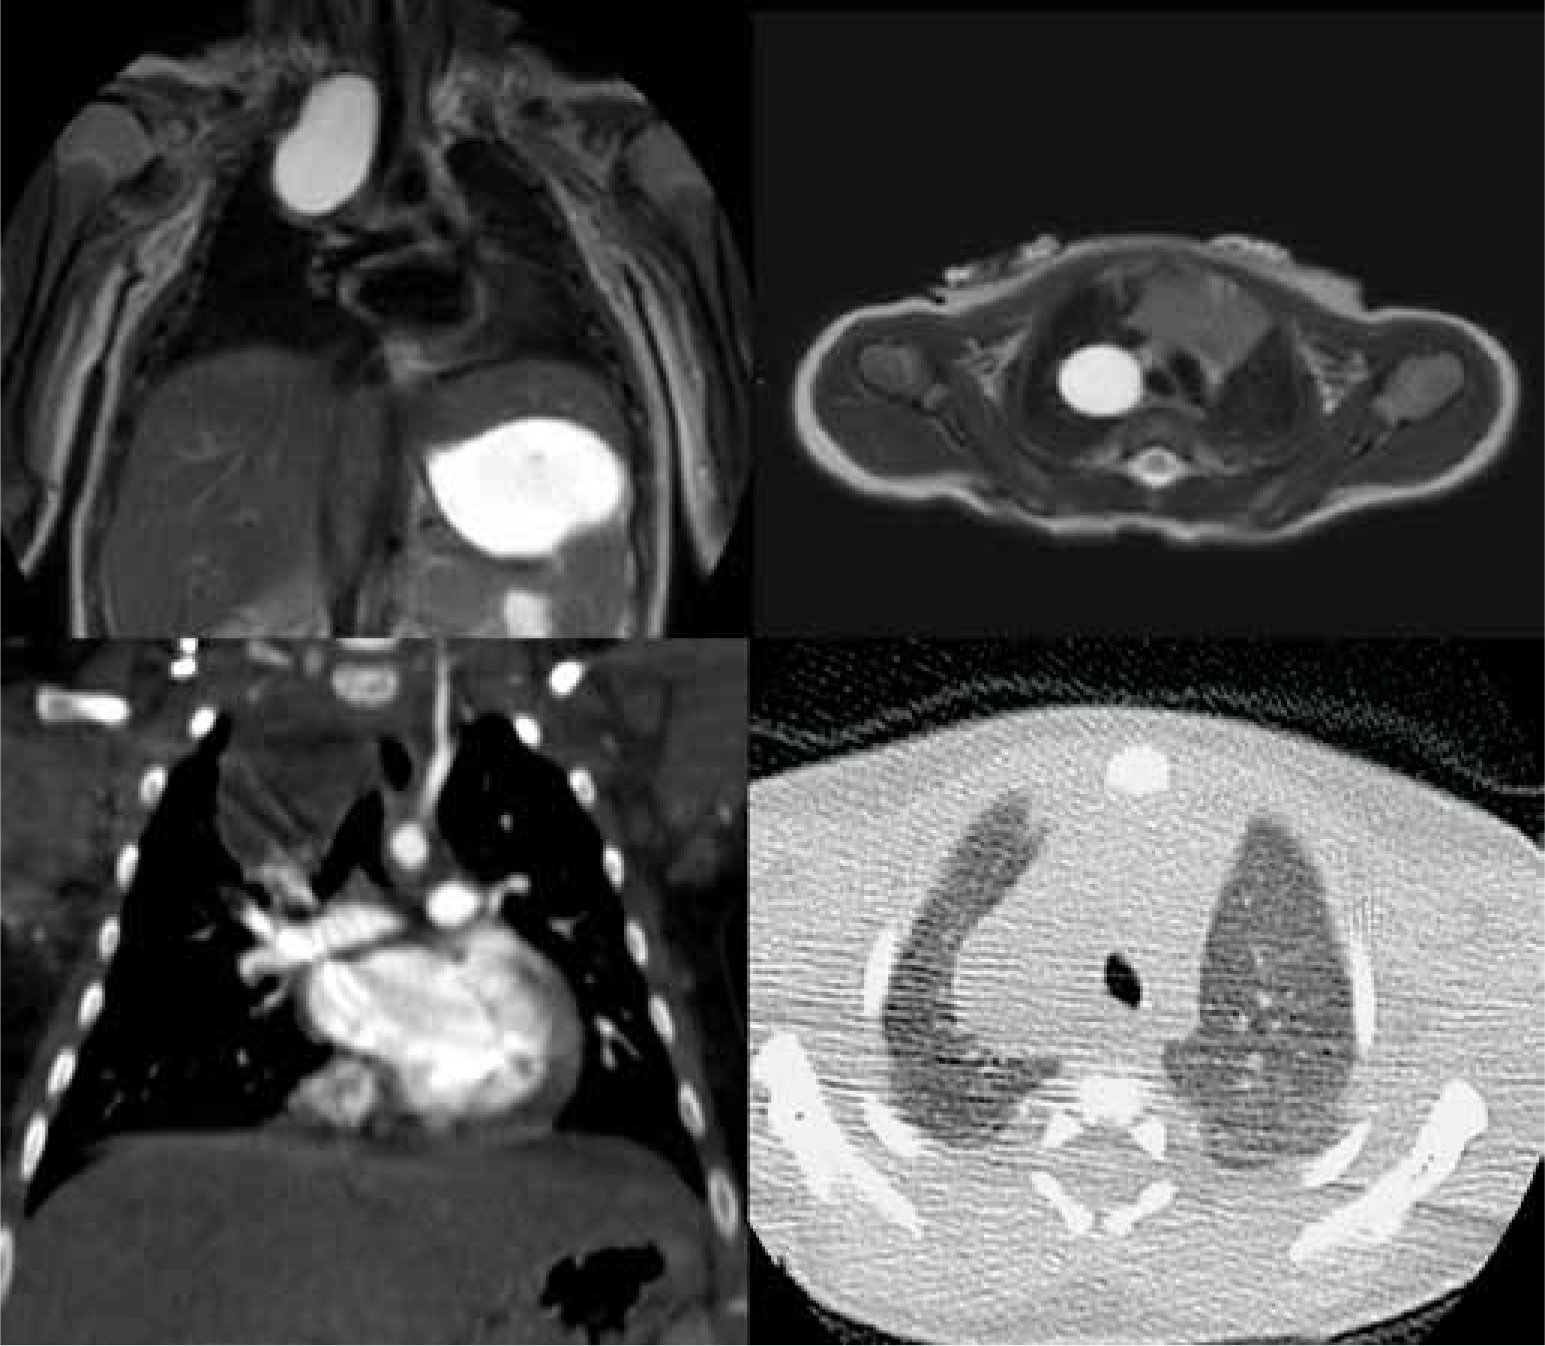

Figure 4

T2-weighted magnetic resonance imaging (up) and contrast-enhanced computed tomography (down) on coronal and axial planes, showing lower left lung extra-lobar bronchopulmonary sequestration. In the coronal plane (left) the venous drainage into the azygous system can be seen. In the axial plane (right) the anomalous artery supply arising from the descending aorta can be seen